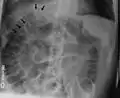

| Frontal chest X-ray. The air bubble below the right hemidiaphragm (on the left of the image) is a pneumoperitoneum. | |

When present, pneumoperitoneum can often be seen on projectional radiography, but small amounts are often missed, and CT scan is nowadays regarded as a criterion standard in the assessment of a pneumoperitoneum.[18] CT can visualize quantities as small as 5 cm³ of air or gas.

Signs that can be seen on projectional radiography are shown below: